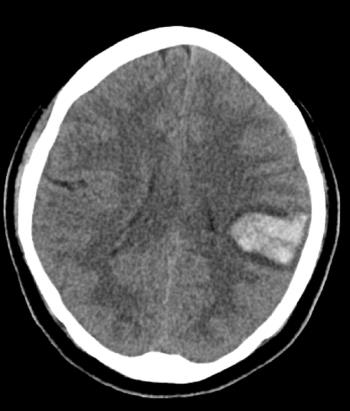

Learn all about intraparenchymal hemorrhage symptoms, causes and treatment. Intraparenchymal hemorrhage is one extension of intracerebral hemorrhage) with bleeding within brain parenchyma.

Intraparenchymal or Intracerebral hemorrhage (ICH) is when blood suddenly bursts into brain tissue, causing damage to your brain. Symptoms usually appear suddenly during ICH. They include headache, weakness, confusion, and paralysis, particularly on one side of your body. The buildup of blood puts pressure on your brain and interferes with its oxygen supply. This can quickly cause brain and nerve damage.

Intraparenchymal hemorrhage accounts for approx. 8-13% of all strokes and results from a wide spectrum of disorders. It is more likely to result in death or major disability than ischemic stroke or subarachnoid hemorrhage, and therefore constitutes an immediate medical emergency. Intracerebral hemorrhages and accompanying edema may disrupt or compress adjacent brain tissue, leading to neurological dysfunction.